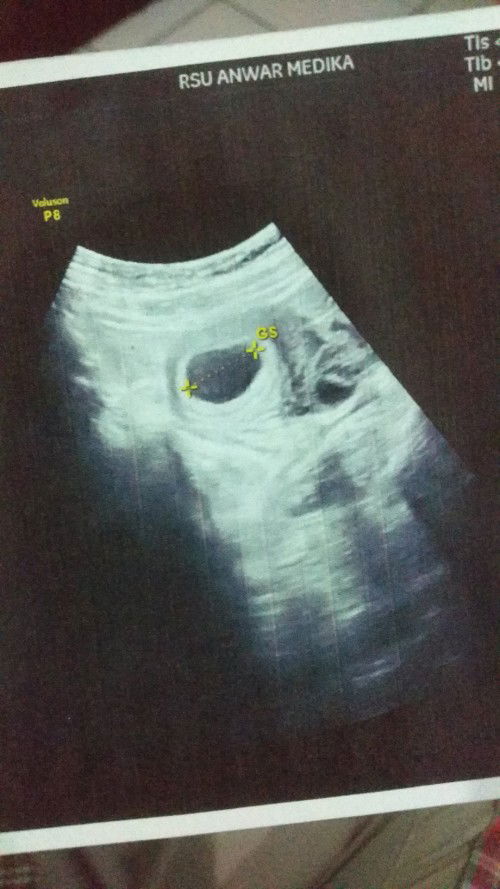

Hallo bunda semua, berdasarkan hpht kandungan saya skrg 7w2d. Semalam baru aja USG tapi hanya terlihat kantung kehamilan aja seperti di gambar, belum kelihatan janin dan djjnya. Tapi di layar USG hitungannya pun sama 7w2d. Apa itu normal Bun? Kapan kira-kira saya USG lagi biar bisa lihat janin+djj nya Saya agak worry Bun, padahal semalam berharap banget uda bisa dilihat janinnya 😢 #seriusnanya #bantusharing #ingintahu #firstmom #pleasehelp #firstbaby